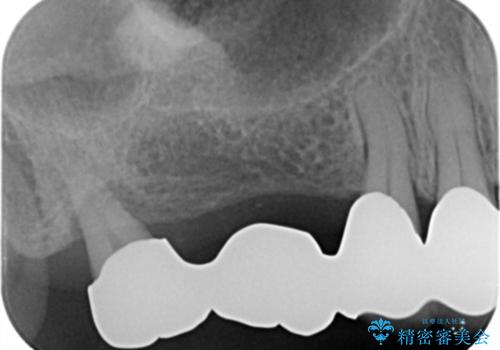

X線写真より、咬合力負担能力に十分で無い親知らずを使用した長いブリッジが装着されており、力の負担に耐え切れずぐらつきが増加してきた状態です。